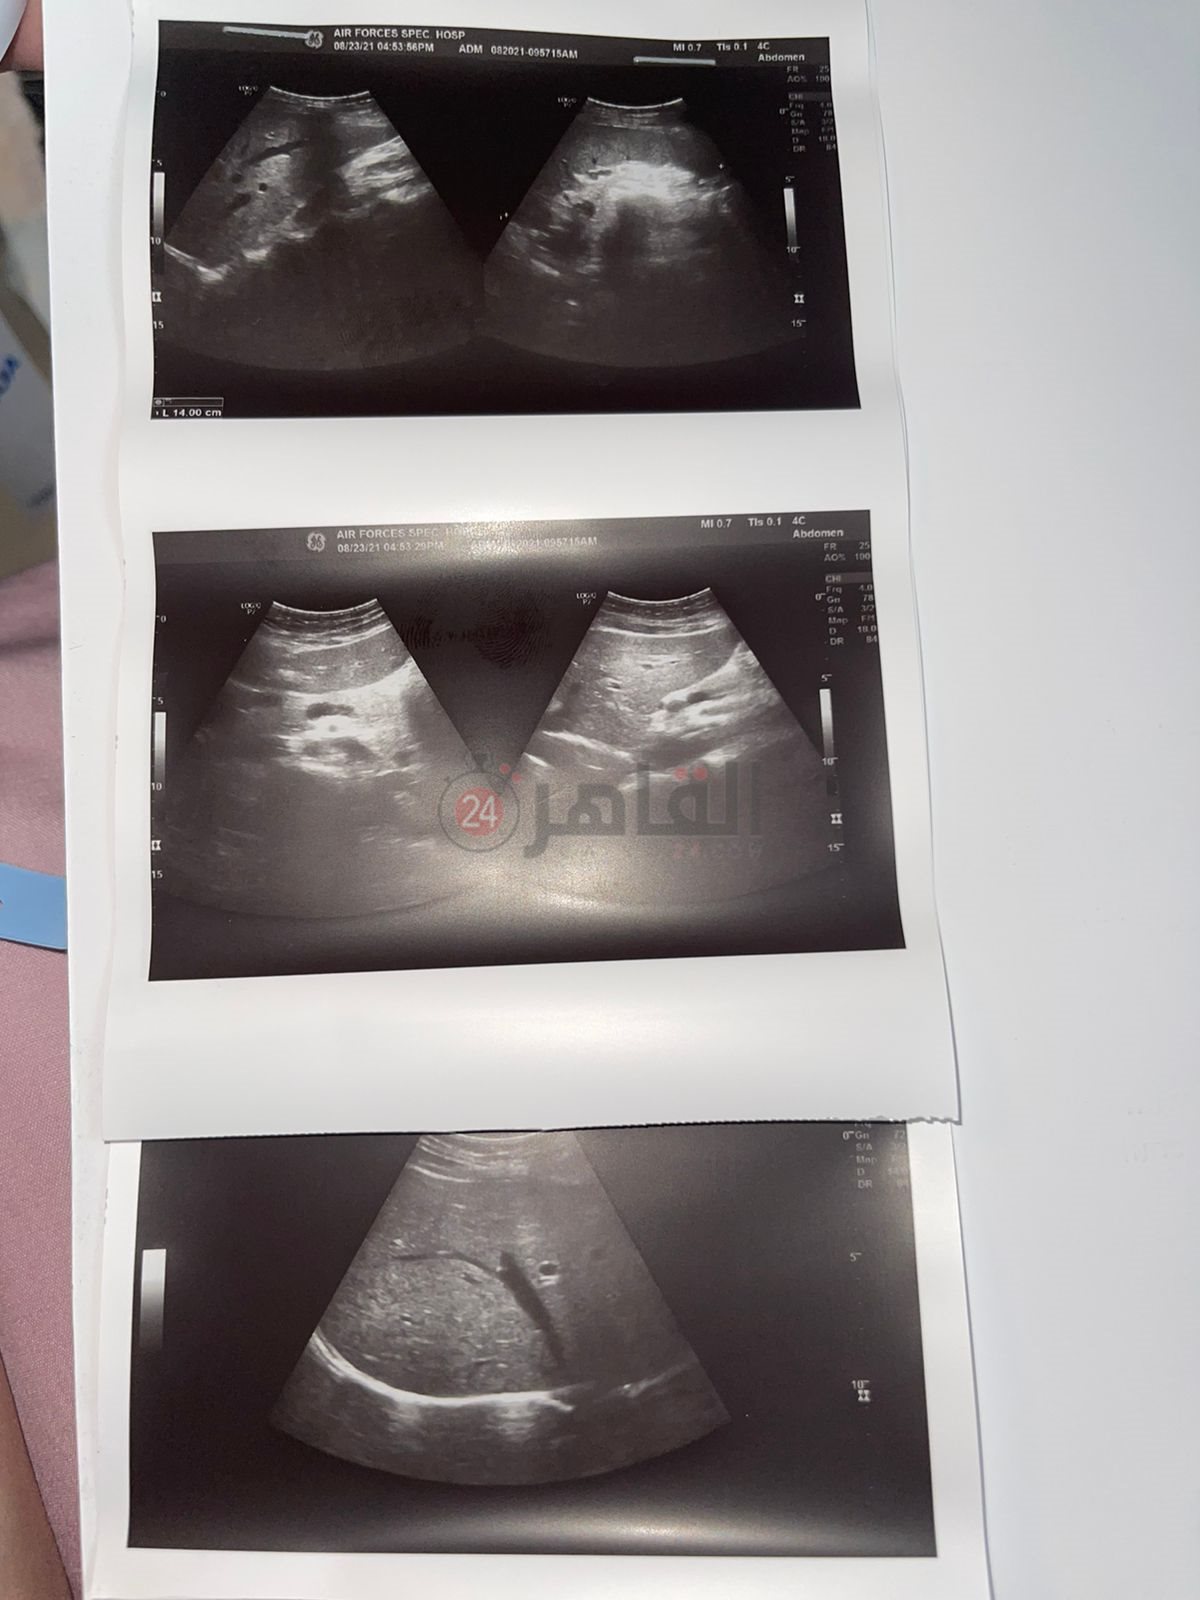

أكدت نصر أنه بعد إجراء العديد من الفحوصات، تبين إصابتهم بمتغير دلتا المتحور من فيروس كورونا المستجد.